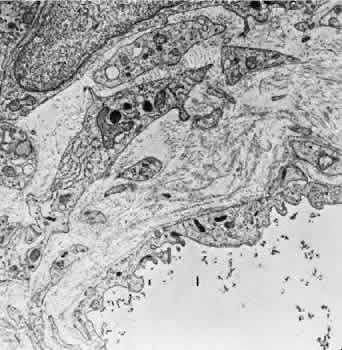

The vessel walls themselves consist of fenestrated endothelium surrounded by a basement membrane and a sparsely arranged layer of pericytes. The portion of the endothelial cell containing the nucleus also contains most of the cell's cytoplasm and organelles. The remainder of the cytoplasm is extremely attenuated, and these regions contain the fenestrae. These fenestrae are approximately 700 to 800 nm in diameter and are covered by a diaphragm. The attenuated areas are most typically found facing the RPE and contain very few pinocytotic vesicles. The region of the cell facing the suprachoroidal space usually contains more cytoplasm, fewer fenestrae, and the nucleus (Fig. 14). Few pericytic processes are seen in cross sections of these vessels on the side of the vessel facing the pigmented epithelium (Fig. 15). However, these processes are more numerous on the surface of the vessel facing the sclera. Because of the fenestrae, the choriocapillaris actively leaks fluorescein molecules.

Fig. 14. Electron micrograph. A. A portion of the capillary wall facing the suprachoroidea. The endothelial layer is relatively thick, and few fenestrae are present. Several pericytic processes (arrows) may be seen. B. A portion of the capillary wall facing the pigmented epithelium. Numerous fenestrae may be seen in the attenuated endothelium. The elastica of Bruch's membrane is well developed (EI).

Fig. 15. Electron micrography of a tangentially sectioned choroidal capillary. The attenuated portion of the endothelial cell may be seen facing the elastica of Bruch's membrane (arrows).